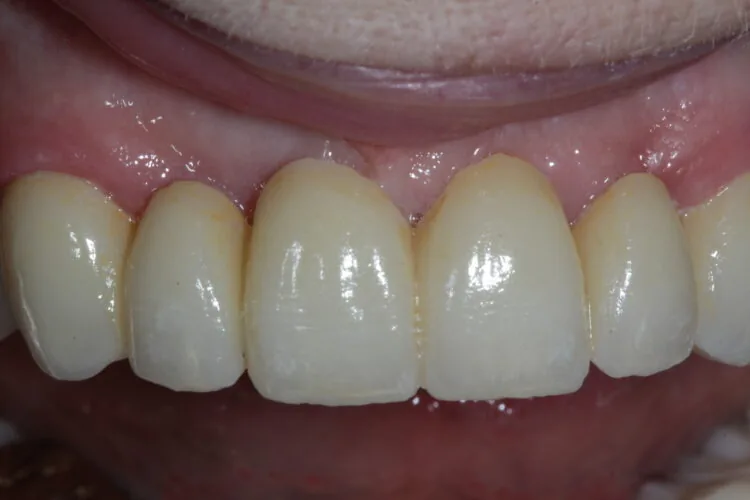

4. After this phase, a definitive six-unit porcelain bridge was placed to restore aesthetics and function.

5. To complete the smile enhancement, porcelain veneers were placed on the premolars to increase the buccal corridor fill and broaden the smile.

Outcome

The final result delivered a dramatic transformation. The bridge and veneers blended naturally, restoring symmetry and confidence to the patient’s smile. Upon seeing the result for the first time, the patient was visibly emotional and described the outcome as far exceeding her expectations.